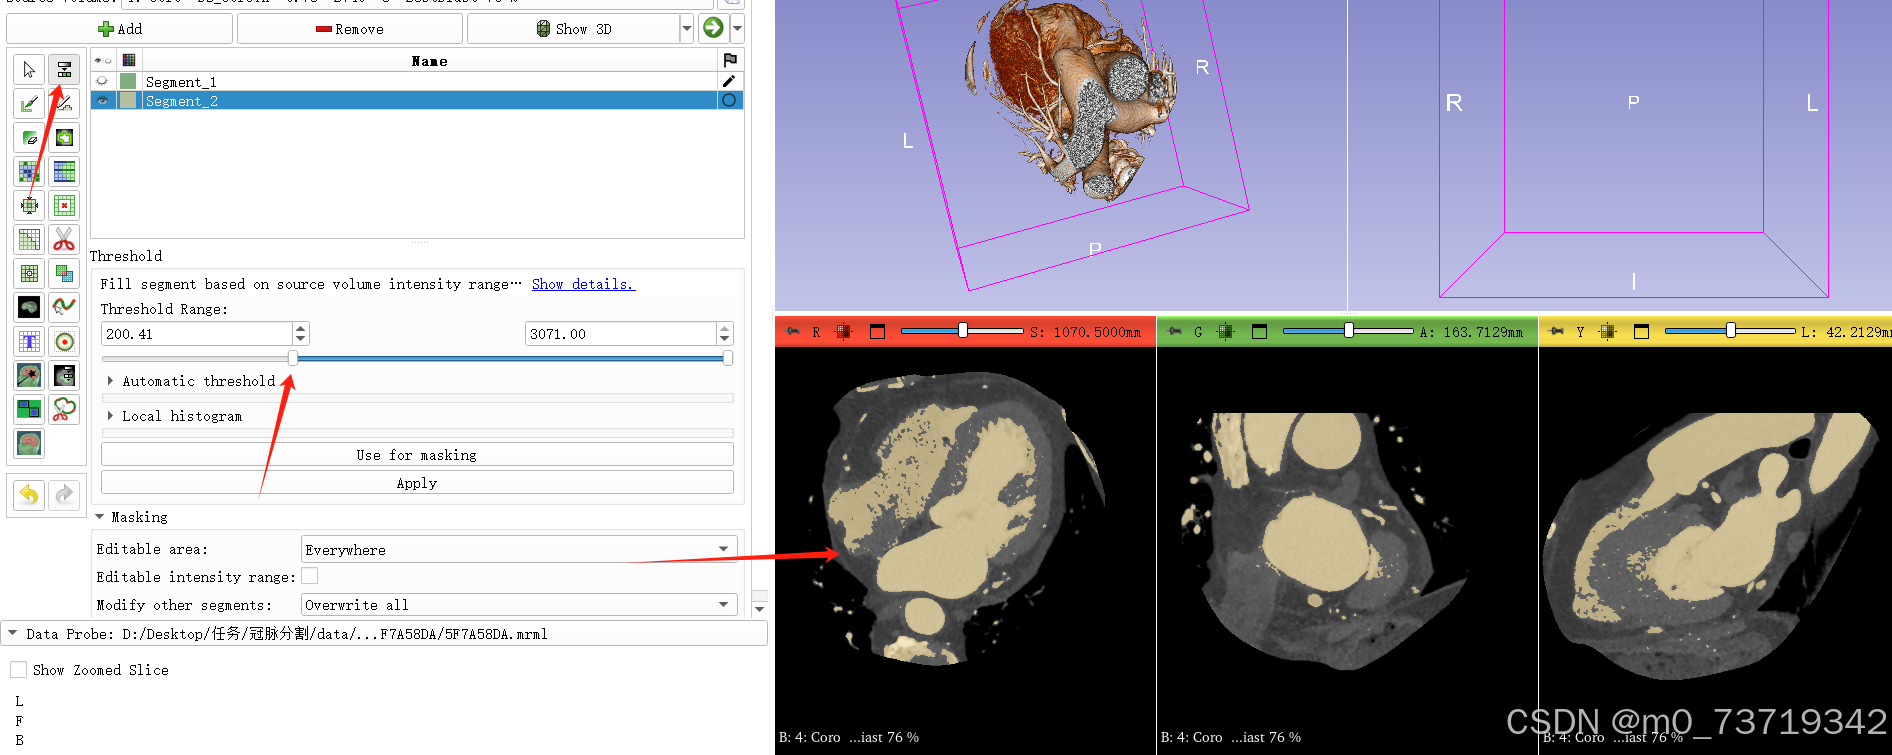

4.阈值分割出完整冠脉区域

新建标注2

点击此按钮调整图像对比度(关闭标签1视图,鼠标左键上下滑动调整至合适对比度即可)

对相关区域进行阈值分割(调整范围至分割区域界限明显,噪点较少即可。该步骤可以在apply之后观看三维视图,阈值不合适可以再次调整至合适为止)

在三维视图中可观看如下